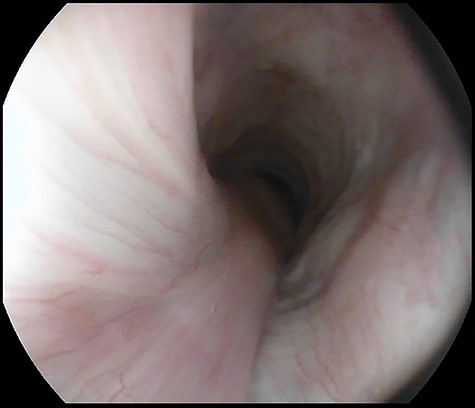

A 69-year-old woman was referred because of recurrent episodes of vomiting with concomitant regurgitation of a fleshy mass in the mouth and multiple episodes of asphyxia. The patient had a long history of heartburn and a GERD-HRQL score of 18. An upper GI endoscopy revealed a long pedunculated polypoid mass covered with normal squamous epithelium (Fig. 6). A computed tomography (CT) scan showed a fat-density mass in the esophageal lumen, originating about 1 cm below the upper esophageal sphincter and extending caudally in the esophageal lumen. A flexible endoscopic procedure was performed under general anesthesia and orotracheal intubation. An endoclip was placed at the base of the stalk in the cervical esophagus, and a snare resection of the pedunculated lipoma was successfully performed (Fig. 7). The procedure lasted 40 min. The patient began a soft diet on postoperative Day 1, which was well tolerated, and was discharged home on postoperative Day 2. Pathology confirmed a preponderant component of adipose tissue with a central fibrovascular core, covered by normal esophageal squamous mucosa (Fig. 8). At the 3 month follow-up visit the patient was asymptomatic, with a GERD-HRQL of 5 under treatment with proton-pump inhibitors.

Pre-operative upper gastrointestinal endoscopy showing pedunculated lipoma arising 1 cm below the upper esophageal sphincter and extending from 18 to 26 cm from the incisors.